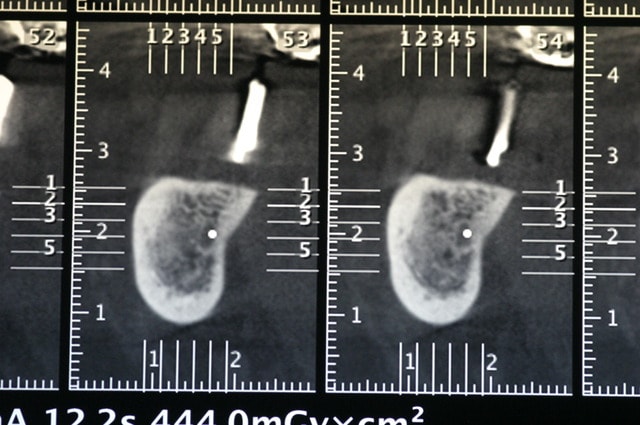

voila, j’espère que c'est lisible.

petites questions: qu'elle types d'implants utilisais tu, et il semblerait sur le planification et sur les scan qu'il y ai plusieurs spires qui ne soit pas enfouies, cela n'a t-il pas de conséquences sur le long terme?

les implants étaient des cylindro conique Anthogyr, le scan n'est pas toujours fiable pour. les faibles. épaisseurs, sur ce. cas il y a une perte osseuse sur. un implant antérieur ou j'ai fais une expansion au piezo et l' os a chauffé car. l' irrigation est mal passée, mais les autres vont bien.